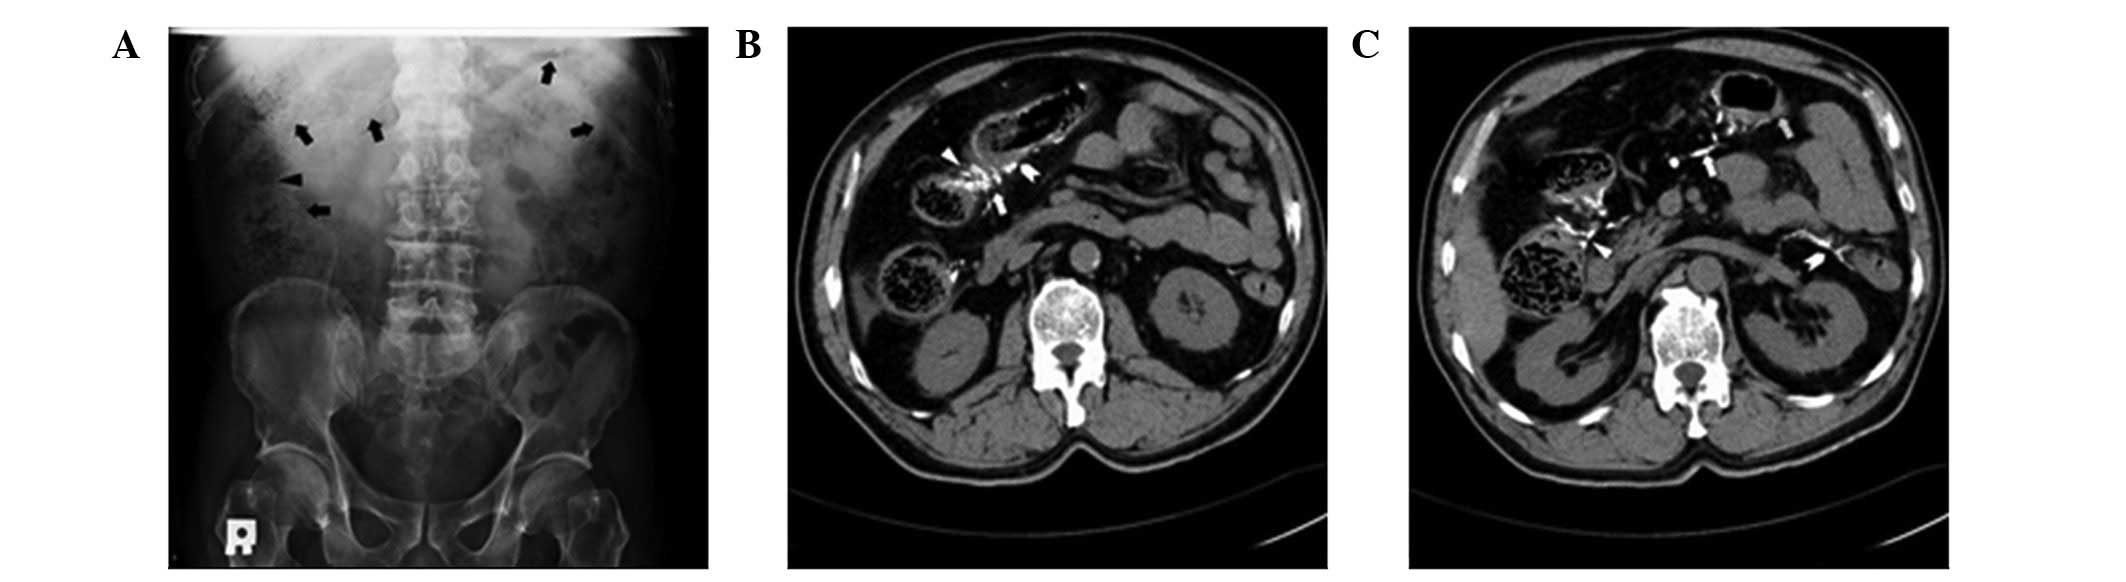

Physical examination revealed stable vital signs and rebound tenderness over the right upper abdomen. Laboratory data, including biochemistry, electrolytes and a complete blood count, were all within normal limits, except for mild leukocytosis [white blood cells (WBCs), 12,600/μl; segmented neutrophils, 70.1%]. An abdominal radiograph revealed thread-like radiopaque densities in the right upper quadrant (Fig. 1A). Computed tomography (CT) revealed numerous serpentine calcifications alongside the colonic veins, which extended from the terminal ileum to the proximal descending colon, ascites, and wall thickening and luminal stenosis over the hepatic flexure (Fig. 1B and C). Compared with the previous imaging studies, the extent of the calcifications had become more severe. Angiography showed a patent superior mesenteric artery trunk; however, there was decreased arterial perfusion and absent venous return at the tributary of the ascending colon and hepatic flexure (Fig. 2).

Figure 1

(A) Abdominal radiograph revealed fecal material in the right colon (arrowhead) with thread-like radiopaque densities representing vascular calcifications over the ascending and transverse colon (arrows). (B) CT revealed numerous serpentine calcifications (arrow) and stenosis (arrowhead) of the hepatic flexure of the colon with wall thickening (arrow tail). (C) CT also showed serpentine calcifications of the superior mesenteric vein and its tributaries of the ascending and transverse colon (arrowhead and arrow). Marked calcification of the inferior mesenteric vein and its tributaries of the descending colon was noted (arrow tail). In addition, wall thickening of the ascending, transverse and proximal descending colon, associated with poor contrast enhancement, was observed (arrow with oblique lines). CT, computed tomography.